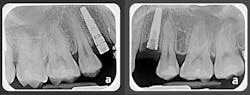

- He had improper buccolingual inclination as most of the posterior teeth had excess lingual inclination (figure 4).

Everything added up to a diagnosis of maxillary deficiency, which had an adverse effect on the position of the mandible. The patient’s narrow, underdeveloped maxilla also trapped his mandible in a retruded position upon closure.

Again, the above diagnostic information was taken into consideration during the consultation process. Since the patient had both foundation and tooth alignment issues, it was determined that he would benefit from a treatment plan addressing both issues. An upper removable expansion appliance would be a good choice to start; however, this patient knew he would not be able to achieve the compliance necessary for the appliance to be effective. Fortunately, clear aligners offer an excellent opportunity for arch development, tooth alignment, and a healthy occlusion.